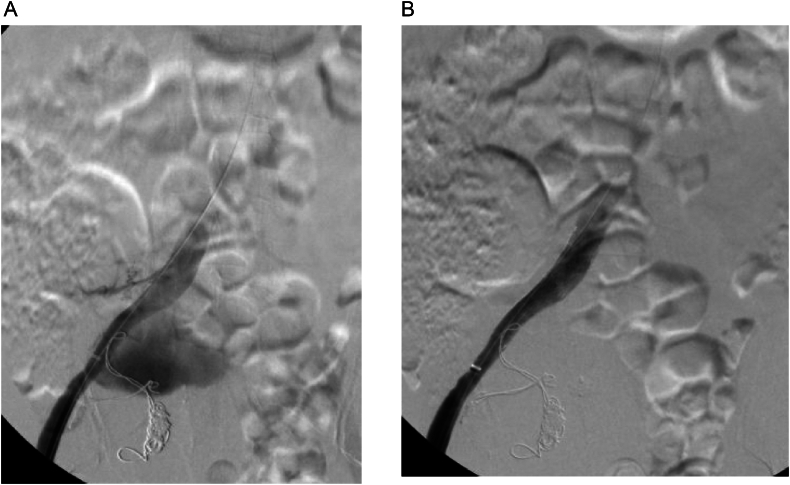

The patient was asymptomatic with an unremarkable abdominal and lower limb examination. Endovascular treatment was conducted utilizing coil embolization of the distal internal iliac artery followed by balloon expandable size (16 × 12 mm × 7 cm, Gore Viabahn VBX) extending from the common iliac to the external iliac artery, excluding the right hypogastric artery. The completion angiogram confirmed the absence of flow into the aneurysm with no signs of endoleak (Fig. 2A and B). Post-operatively, the patient was prescribed dual anti-platelets (once-daily oral Aspirin 81 mg and once-daily oral clopidogrel 75 mg) and was followed up in an outpatient setting. Eight weeks after the procedure, the patient was admitted to another local hospital due to upper gastrointestinal bleeding and a pulsatile abdominal mass in the right lower quadrant. A CT angiogram was conducted and showed an increase in the size of the previously excluded right internal artery aneurysm to 12.9 × 10 cm (Fig. 3). The stent was patent, with suspicion of type IIa endoleak and contrast retention in delayed images. Subsequently, the patient was taken for a conventional angiogram. It was observed that contrast was pooling within the aneurysm, with pelvic and thigh collaterals originating from the proximal right profunda femoris artery supplying the aneurysm (Fig. 4A and B), and therefore, the branch was embolized and despite that, type IIa endoleak persisted in the follow-up CTA. His case was discussed in a multidisciplinary meeting, and the decision was to proceed with open surgery to control the feeding source and to decompress the compressing aneurysm. He was electively brought to the operation room for exploratory laparotomy.

Fig. 2.

(A) Angiogram before stenting. (B) Completion angiogram revealed no flow to the aneurysmal sac.

Fig. 4.

A and B: Type IIa endoleak via right profunda femoris artery (white arrow).